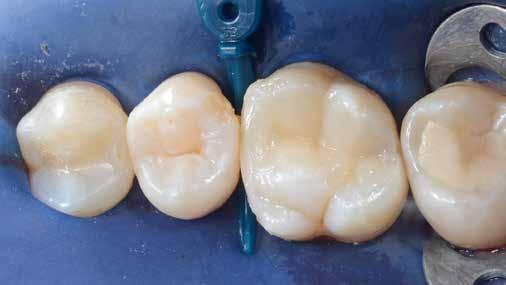

Az 53 éves hölgy páciens jobb felső 6-os fogában látható amalgámtömés cseréje volt a cél. A tömés mellett secunder caries és az amalgám következtében létrejött mesialis zárólécen áthaladó repedés, továbbá mesialis caries figyelhető meg (1. ábra). El kellett kerülni, hogy a tömés kifúrásakor az amalgámtörmelék a páciens szájába kerüljön, esetleg ebből valamennyit lenyeljen, a kezelés első lépésként kofferdám izoláció került fel a jobb felső kvadránsba (2. ábra). A kapocs a 1.7 fogra került, ezzel kényelmesen helyet teremtett a későbbiekben felkerülő matricarendszernek. Az egyszerre több fog izolálása lehetővé teszi, hogy a szomszédos fogak referenciául szolgáljanak a restauráció felépítése közben.

A régi amalgámtömés eltávolítását követően caries indikátor segítette a carieses laesio megfelelő kitisztítását a pulpa expozíciója nélkül. Ezután kerülhetett sor az ideális üregdesign kialakítására, továbbá a zománcszélek finírozására (3. ábra) Az approximális box megnyitása során az alátámasztatlan zománcprizmák eltávolításra kerültek, ezzel is csökkentve a secunder caries képződés veszélyét. Az így kialakuló forma elősegíti a matrica megfelelő adaptációját, végül pedig az approximális box határainak a hozzáférhetőségét, így finírozás során ez jobban kontrollálható és polírozható.

A Palodent V3 matricarendszer felhelyezését követően a zománc 10 másodperces szelektív savazása, majd lemosása és leszárítása után történt a kavítás bondozása Prime & Bond Universallal.

Kulcslépés: a II. osztályú üreget a matricarendszer segítségével I. osztályúvá lehetett átalakítani.

A pontosabb széli záródás érdekében célszerű a matrica illesztési határába némi folyékony kompozitot felvinni (NeoSpectra ST flow A2), majd megvilágítás nélkül a zárólécet paszta kompozittal (NeoSpectra STHV A2) felépíteni, miközben a kifolyó fölösleges folyékony kompozit eltávolításra kerülhet. Így ki lehetett használni és kombinálni a két különböző konzisztencia előnyeit.

A polimerizációt követően kerülhet sor a matricafeszítő gyűrű, valamint a matrica eltávolítására. A Palodent V3 fülekkel ellátott matrica kialakításának és a speciális PinTweezers csipesznek hála, a feszes kontaktpont ellenére a matrica könnyedén eltávolítható. Az éket viszont a kezelés végéig

célszerű bennhagyni, elkerülve egy esetleges nemkívánatos vérzést (4. ábra)

A matrica és gyűrű nélkül az approximális fal magassága, valamint a szomszédos fogakhoz viszonyítható dimenziók jobban megállapíthatóak. A jobb térlátás és a nagyobb mozgástér precízebb eredményhez vezet, csökkentve ezzel az utólagos finírozás mértékét, továbbá a részletgazdagon kialakított anatómiai struktúrák torzulásának az esélyét. Az üreg mélyebb részei SDR Plus A3-mal kerültek feltöltésre, majd NeoSpectra STLV A3-mal kiegészítve vált teljessé a dentin pótlása (5. ábra), ezzel létre lehetett hozni egy homorú formájú kromatikusabb alapot.

Ezt követően csücsökről csücsökre haladva a felső hatosokra jellemző anatómiai struktúrák, megfelelő orientációval bíró csücsöklejtők és elsődleges barázdák Neo Spectra

HV A2 anyagból kerültek kialakításra (6. ábra). Apró „kompozit-hurkákkal” kiegészítve létrehozható a csücskökön belüli tagoltság, ezzel kialakítva a másodlagos barázdarendszert és egy sokkal kidolgozottabb anatómiai struktúrát (7. ábra). A fogorvos esetleges „művészi hajlamát” is figyelembe véve, a természethű megjelenés barázdafestéssel (Micerium - Stain Brown 2) még tökéletesebb lehet (8. ábra). Ezzel a korábban részletgazdagon kialakított ba-

rázdarendszer kiemelhető, és optikailag fokozható a gödröcskék mélysége is.

A restauráció megfelelő polimerizációja után célszerű a kofferdám nyújtotta retrakciót kihasználni, és a restauráció széli záródásában levő esetleges kompozitfölösleg elfinírozását jobb rálátás mellett elvégezni (9. ábra). Ebben nagy segítségünkre lehet az Enhance rendszer, mely a kompozitot nagyon szépen elsimítja, de a természetes fogszövetet nem bántja.

A matricázott terület széli záródásának a kidolgozásában az EVA polírozó (10. ábra) lehet a segítségünkre, amellyel a gingiva sérülése megelőzhető, és a kialakított feszes kontaktpont sem kerül redukcióra (11-12. ábra)

A kofferdam eltávolítását követően kerülhetett sor az occlusio beállítására csücsöklejtők domborúságának a redukciója révén (13. ábra). A harapás gyémántfúrókkal történő beállítása után a polírozás Enhance rendszerrel történt, melynek végső lépéseként a PrismaGloss használatával (14. ábra) nyerhette el a restauráció a végső fényességét (15. ábra)

A ma rendelkezésre álló modern eszközöknek és anyagoknak hála II. osztályú üregek direkt módon kiszámíthatóan restaurálhatóak. A matricarendszernek köszönhetően helyreállítható a feszes kontaktpont, a „kaméleon effektussal” bíró kompozit pedig a tömés integrációjáért felel. A megfelelő adhézió, a precízen kidolgozott széli záródás és a plakkréteg megtapadását nehezítő polírozott felszín a kezelés hosszú távú sikerének a garanciája. Mindezek együtt egy hosszú távon tartós, funkcionális és esztétikai rehabilitálást tesznek lehetővé.